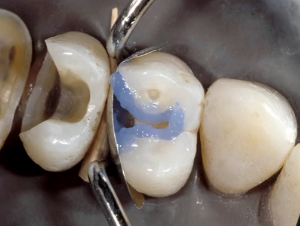

Verify adequate coverage

After light-curing the bonding agent, it’s essential to verify adequate coverage. A tooth that is adequately covered will have a shiny surface all over the dentin; if you don’t see any shine, apply another layer of adhesive on top and repeat the process of drying and light-curing until it yields the results you want. Remember, we have to seal the tubules to prevent postoperative sensitivity.

Place first layer of composite

There is ample evidence that bulk-filling techniques are successful — and with the newer low-shrink materials, likely even better then ever — but I personally like to use incremental placement. I start off by placing the composite along the buccal and lingual walls of the proximal box, extending up and along the buccal and lingual walls of the occlusal as well (essentially leaving the middle of the prep unfilled). This layer is cured completely before the second increment.